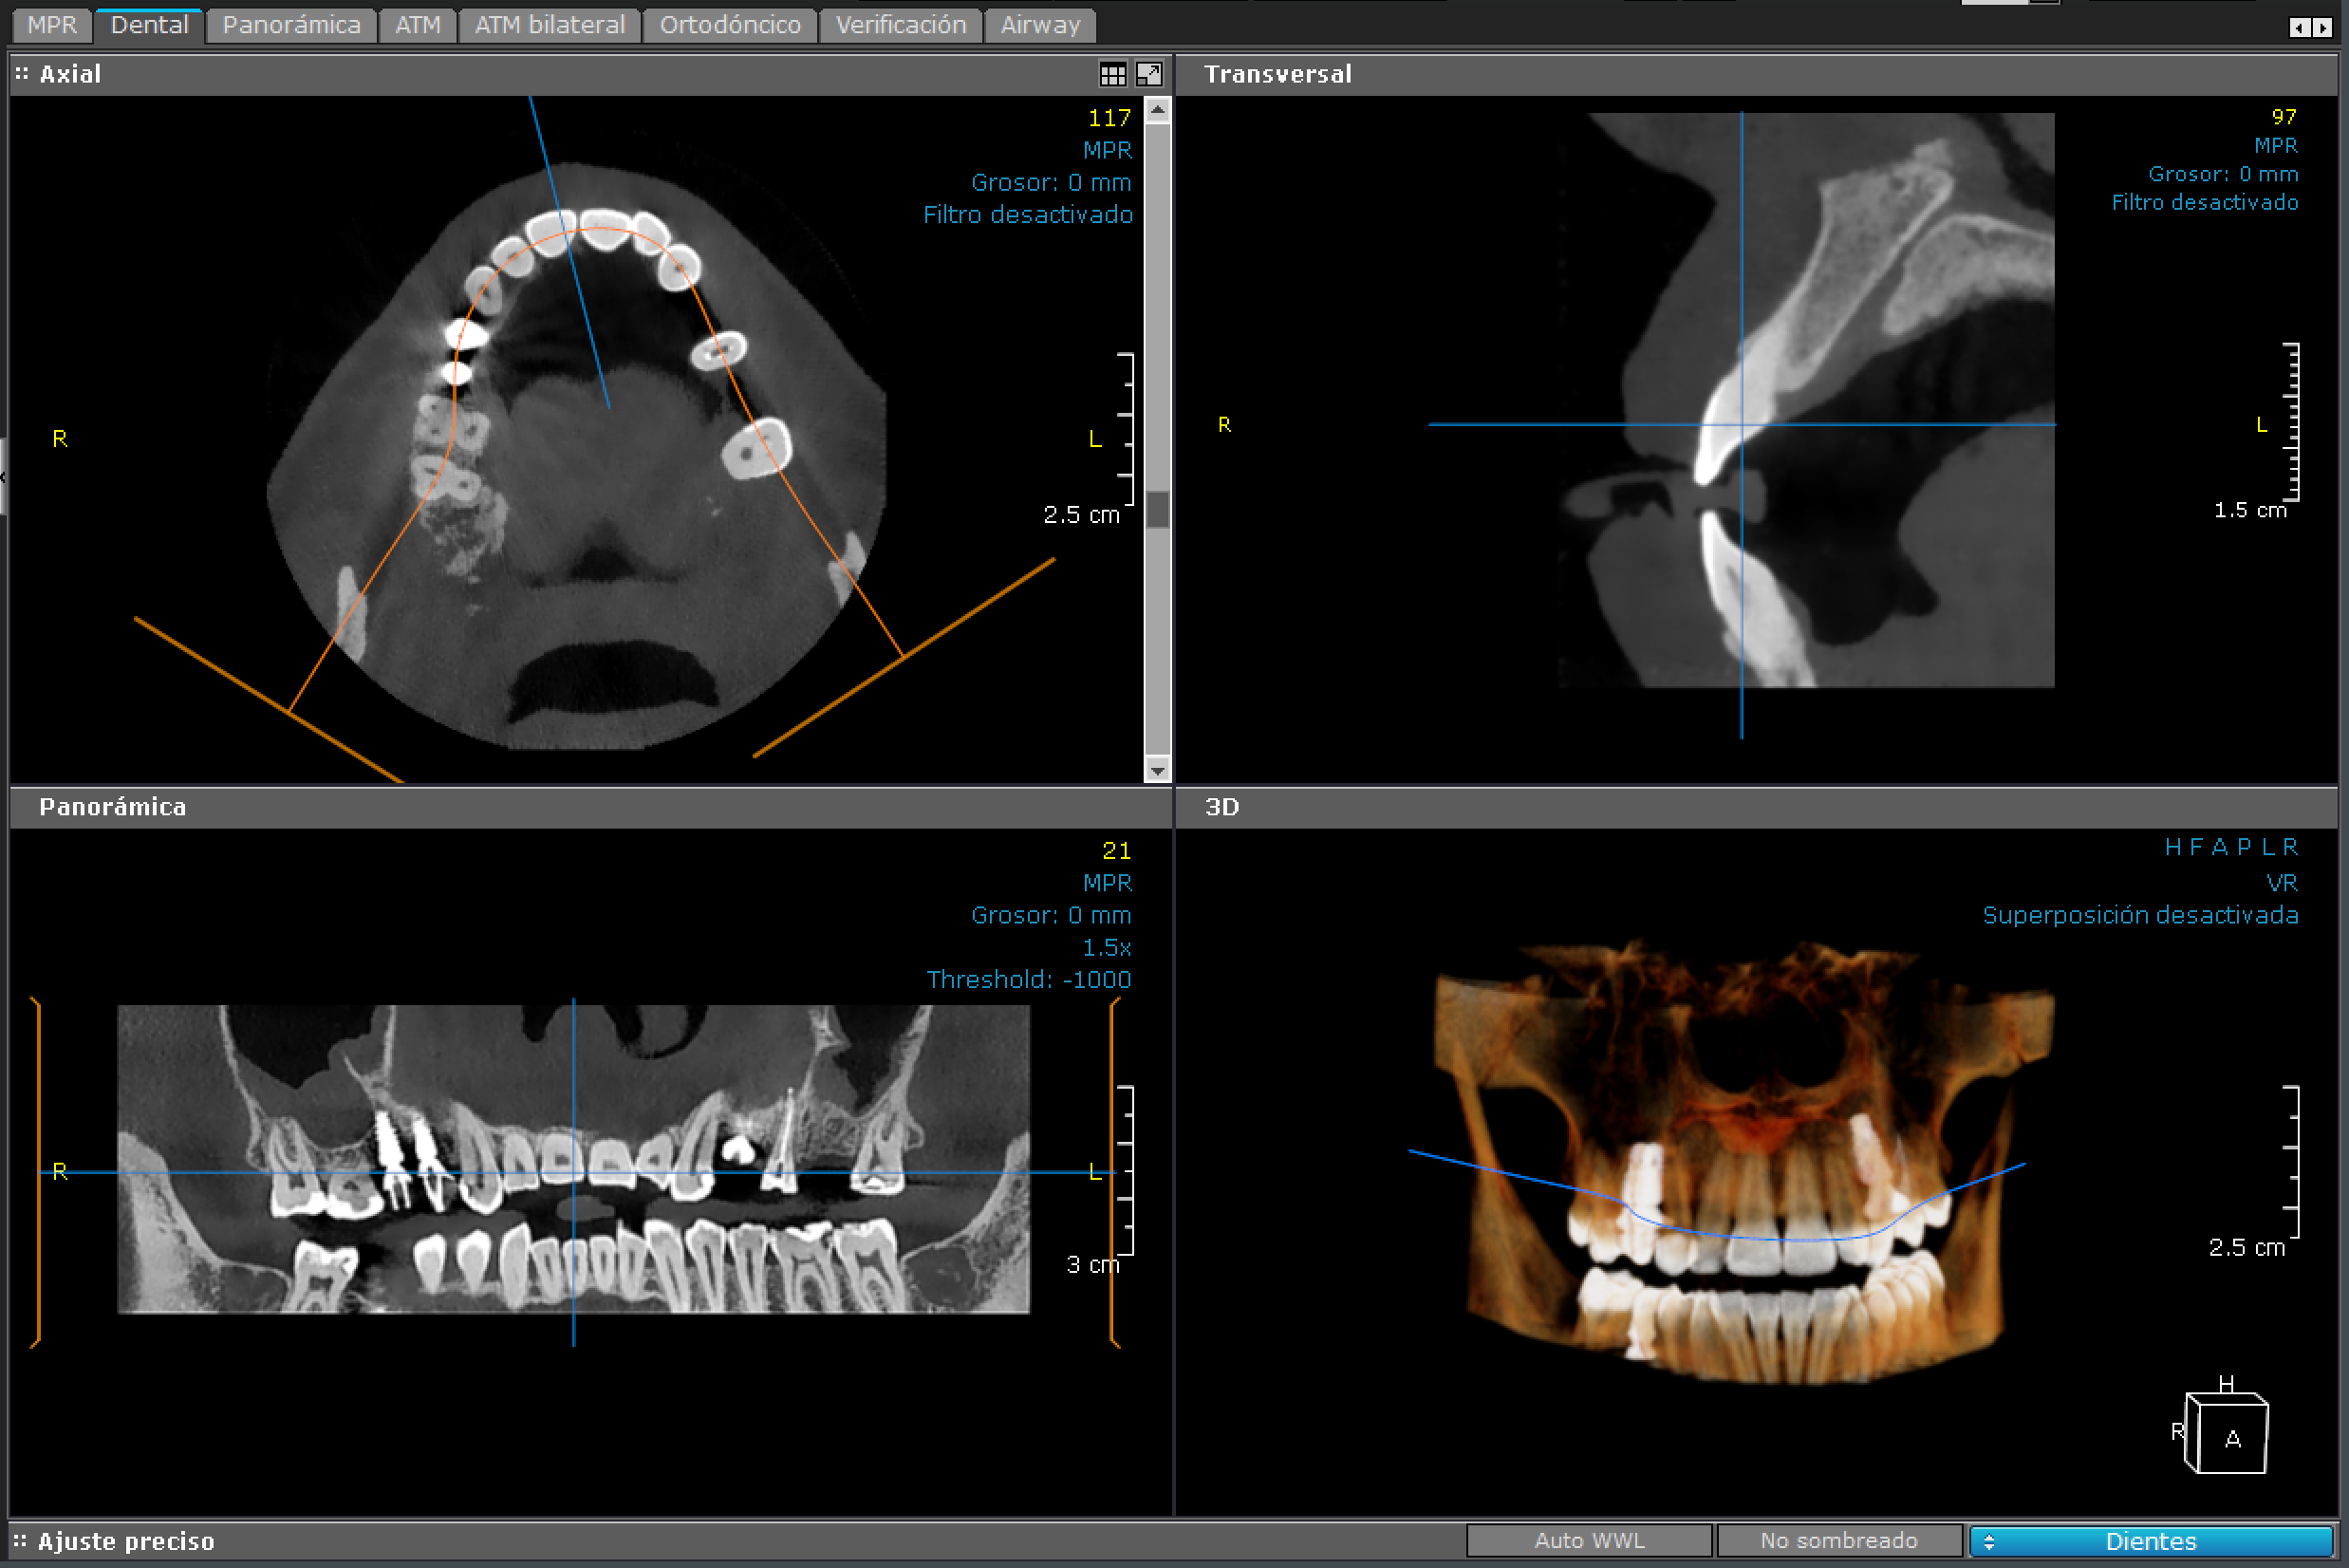

3D - Maxilar Superior

maxilar superior

Esta imagen está centrada en el maxilar superior.